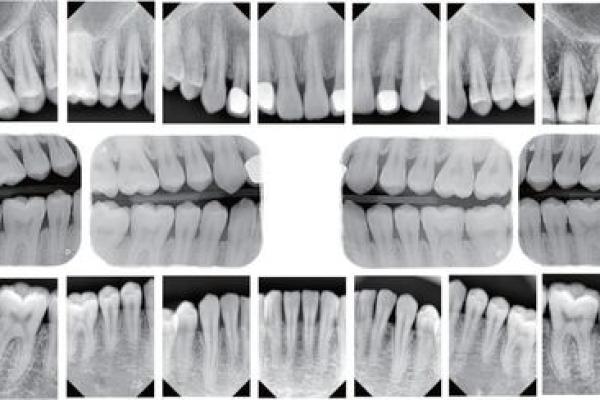

首先,我们来了解男生的牙齿结构。通常情况下,人类的成年人的牙齿数量应为32颗,但有些男生可能因为遗传、疾病或其他因素,只有30颗牙。从相学的角度来看,缺失的牙齿部位可能代表着某种人生的缺憾或劣势。比如,前牙的缺失可能暗示着在爱情上遇到挫折,而后牙的缺失则可能与事业发展受阻有关。这样的相关性虽然并不科学,却也让人倍感趣味。

我们再来深入讨论牙齿的外观特征。牙齿洁白整齐的男生,往往给人一种自信、积极向上的印象。他们在社交场合中更容易获得他人的认可和喜爱。而那些牙齿不整齐、牙黄或存在蛀牙的男生,可能在心理上感到自卑,进而影响到他们在职场上或交友方面的表现。由此可见,良好的口腔卫生和美观的牙齿确实可以在一定程度上提升一个男生的自信心和魅力。

除了形态与数量,牙齿的健康状况同样也影响着一名男生的命运。定期的牙齿检查、及时的口腔护理不仅能防止口腔疾病的发生,还能在社交中提升个人形象。调查表明,牙齿健康的男生在职场中更容易赢得机会。例如,一次商务谈判中,一口整齐的牙齿会使对方对其产生信任感,进而促进合作的达成。